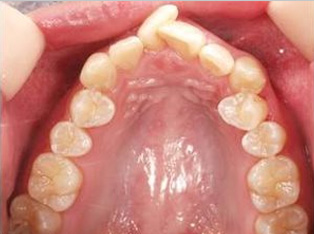

でこぼこがある状態になります。乱ぐい歯とも言われます。見た目がよくない審美障害が主な問題点ですが、その他にもでこぼこが多いことで、歯ブラシによる清掃性が悪くなり、結果、虫歯や歯周病のリスクも上がってしまいます。治療期間が短く済むことも多い為、気になった段階で早期に相談された方が良いと思います。

治療前

治療終了前